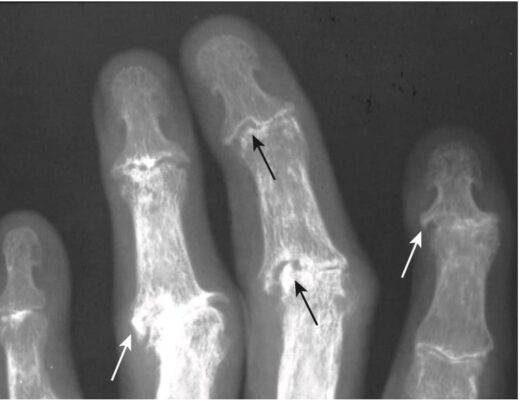

- Các ăn mòn thường nằm ở giữa trong khớp và kết hợp với các gai xương nhỏ, có thể tạo nên dấu hiệu gọi là biến dạng cánh mòng biển (gull-wing deformity) (Hình 8).

- Thoái hóa khớp ăn mòn thường xảy ra nhất ở các khớp liên ngón gần và xa của các ngón tay, khớp cổ -bàn ngón 1, và khớp liên ngón của cái.

- Có thể xảy ra tình trạng dính cứng khớp (bone ankylosis), một dấu hiệu ít gặp trong bệnh thoái hóa khớp nguyên phát.

Hình 8. Thoái hóa khớp ăn mòn. Các dấu ăn mòn thường nằm ở trung tâm trong khớp (mũi tên đen) và kết hợp với các gai xương nhỏ (mũi tên trắng), tạo nên biến dạng cánh mòng biển.